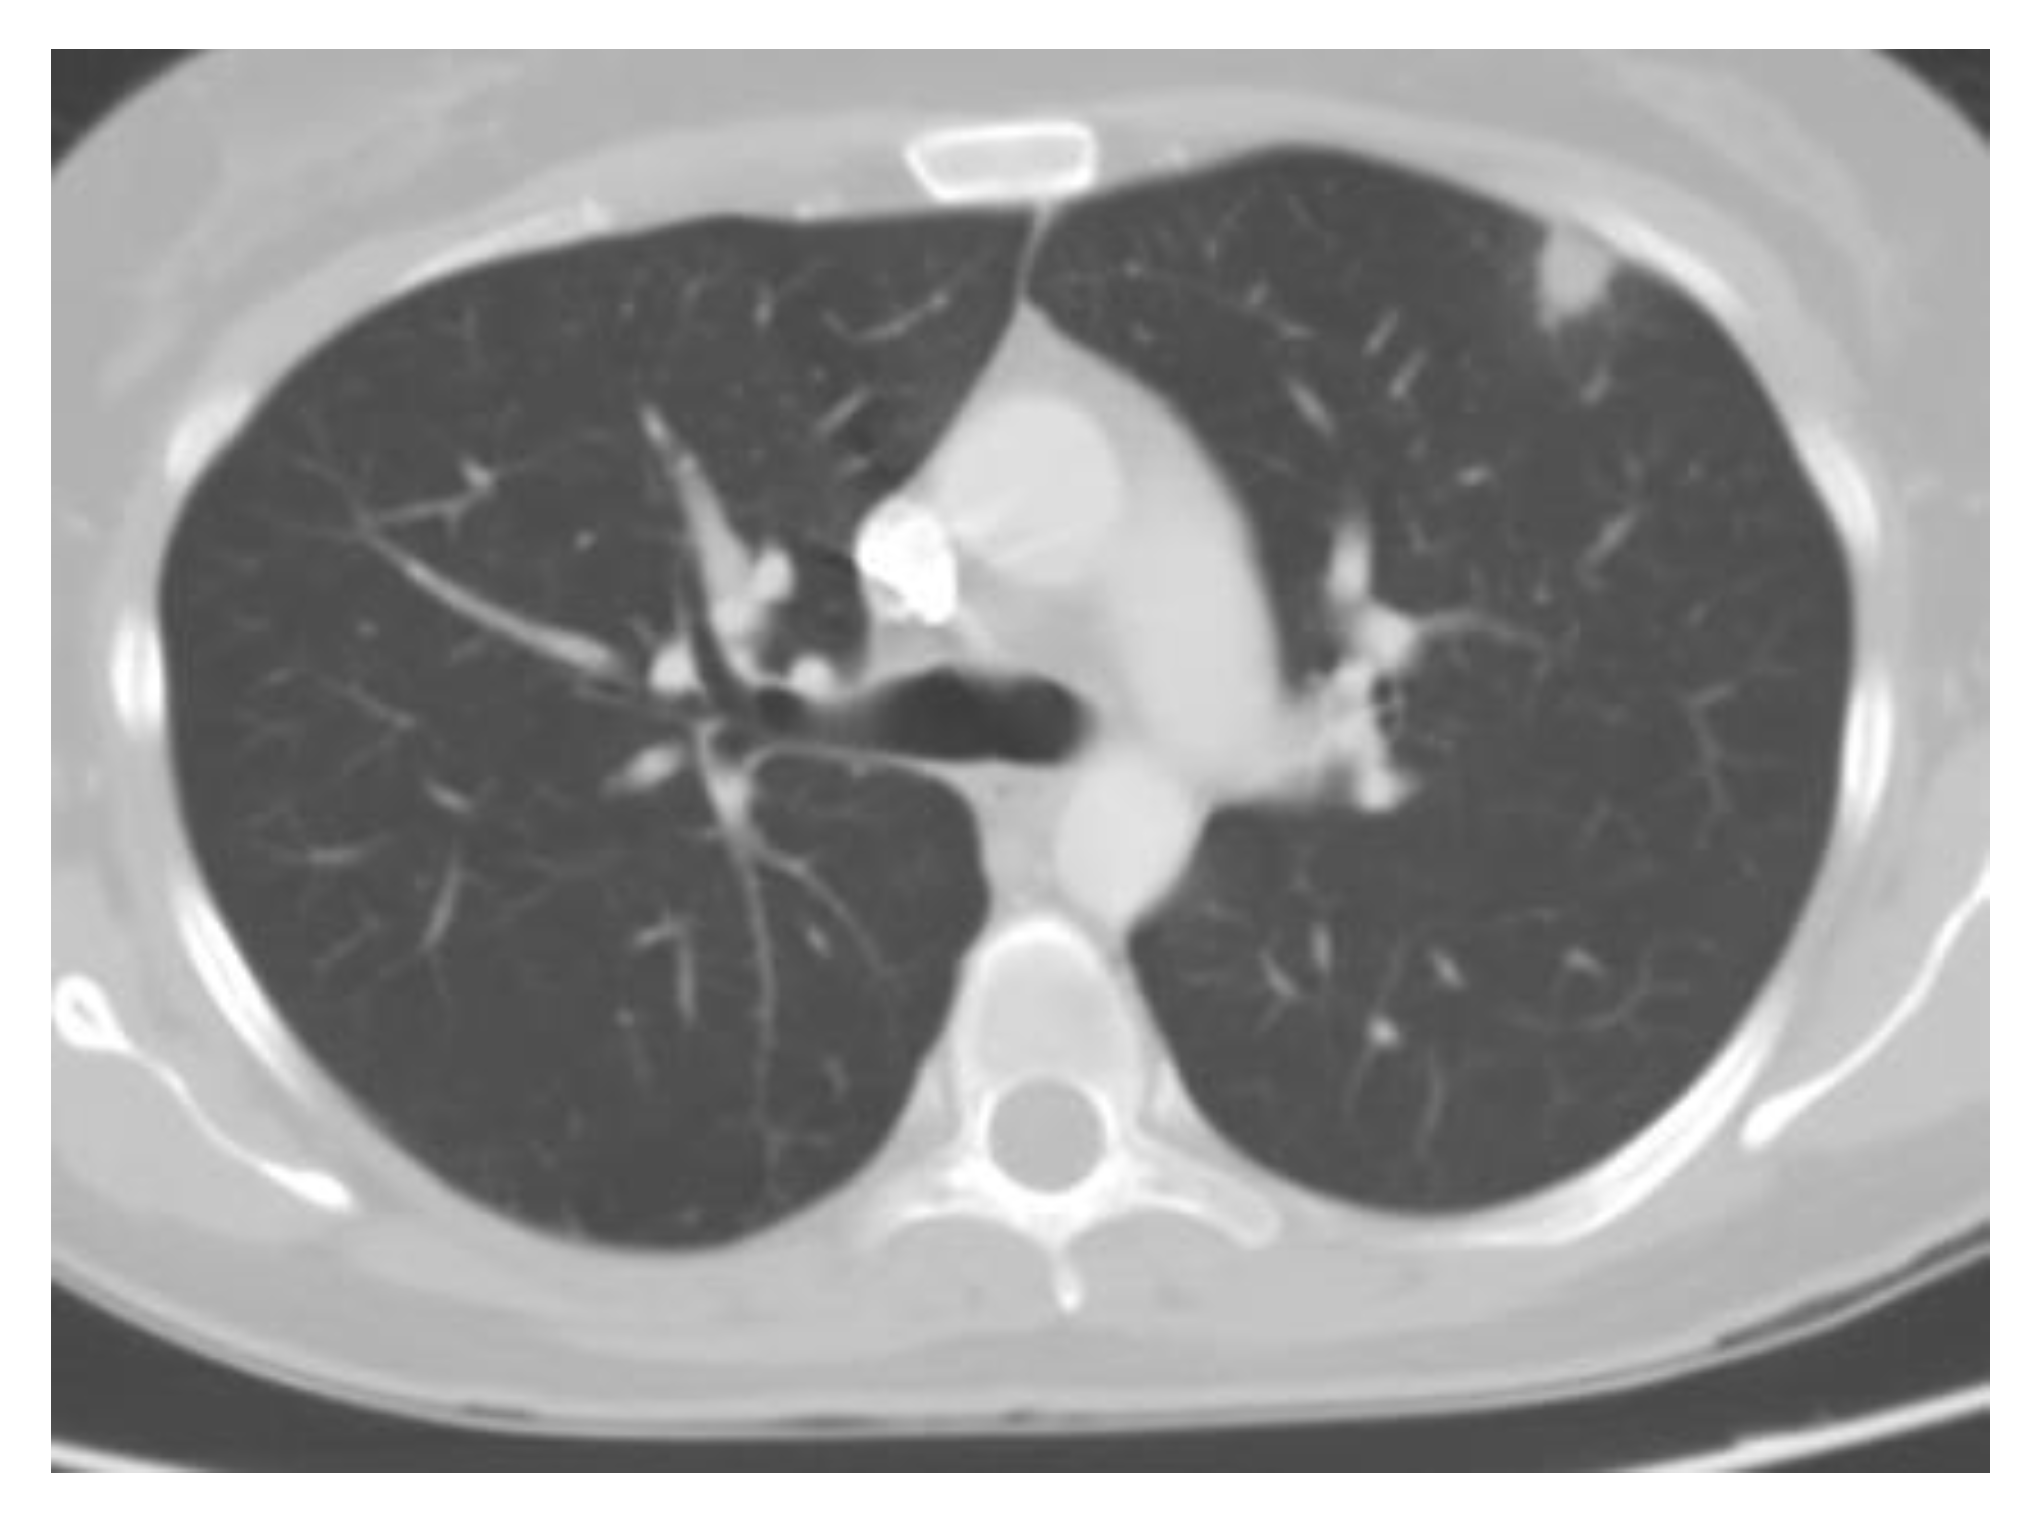

4.1.2. Pulmonary Nodules

Pulmonary nodules are a frequent finding in patients with resolved histoplasmosis and can be seen in up to 57% of the population in endemic areas with occupational exposures [56] (Figure 5). This nodule can occasionally contain no live organisms [57,58]. This poses a significant clinical challenge for the evaluation of patients in endemic regions. In a study of resected pulmonary granulomas of unknown cause, the most common identifiable etiology was histoplasmosis [59]. Rheumatological diseases, including sarcoidosis, may have a similar appearance and are part of the differential diagnosis [60]. Histoplasmosis must be excluded prior to the initiation of immunosuppressive therapy, as the use of corticosteroids can lead to progressive disseminated disease [61]. Most often, the nodules demonstrate several calcifications [57].

Figure 5.

Incidental pulmonary nodule in a patient from a highly endemic area. Biopsies often reveal granulomatous changes and calcifications.